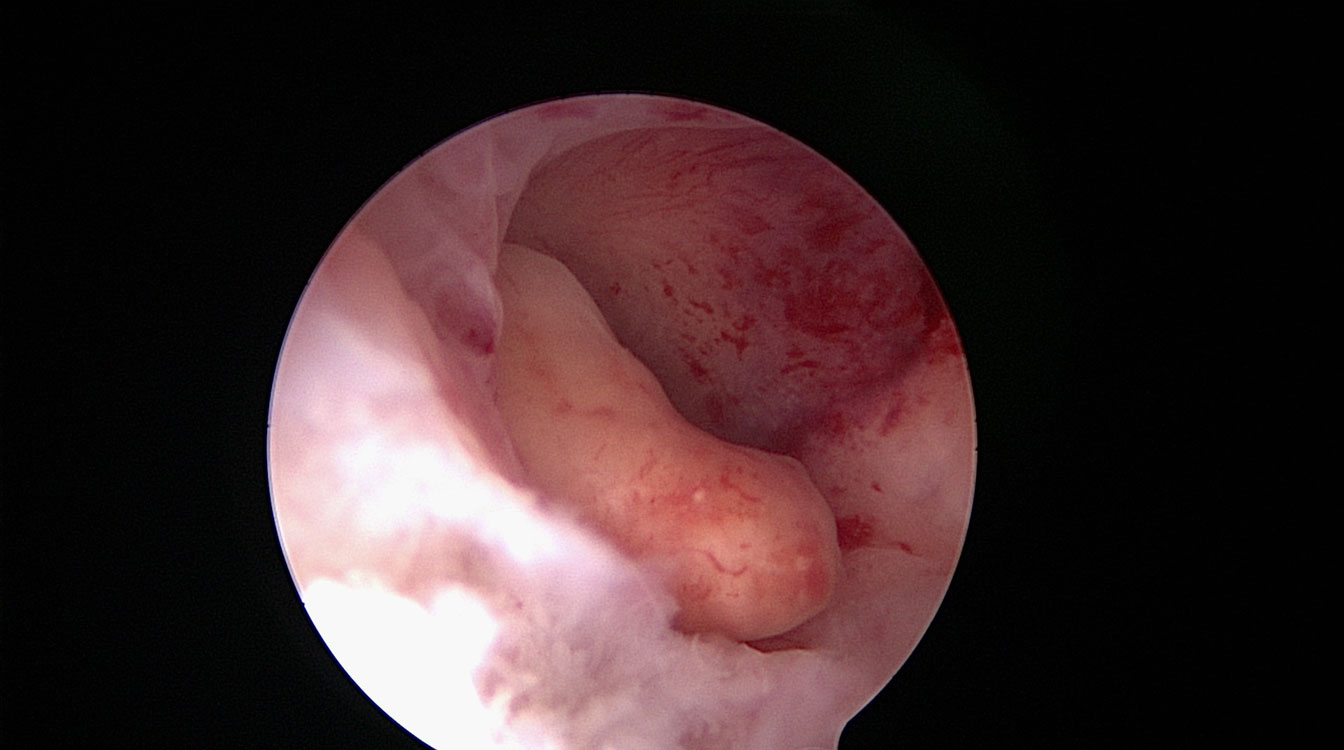

Fibroame uterine

Atunci când se dezvoltă în cavitatea uterină sau în imediata apropiere a cavității, fibromele pot provoca infertilitate, avort spontan recurent, sângerări anormale și dureri menstruale severe.

Astfel de fibroame sunt numite intracavitare sau submucoase. Prezența lor poate fi confirmată prin ecografie sau sonohisterografie (introducerea unei soluții saline intrauterine în timpul ecografiei) sau prin vizualizare directă cu un histeroscop (fig. 5).

Fibroamele pot fi rezecate în fragmente mici, cu ajutorul unor anse electrice în cadrul histeroscopiei, procedeu numit rezectoscopie (fig. 6). Fragmentele rezecate sunt colectate din cavitatea uterină și trimise la laboratorul de anatomie – patologică pentru diagnostic histologic. Cavitatea uterină are aspect normal după operație, crescând foarte mult probabilitatea unei sarcini reușite.